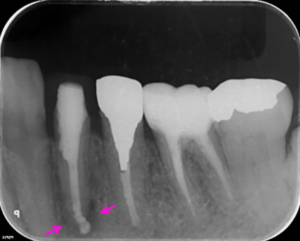

左下4番の歯の根の中を清掃し終わった後に内部に薬を詰めた直後のレントゲン写真です。

薬は根の中に緊密に詰まっています。根管形態が複雑ではなかったため1回の根管治療で治療完了しました。根の先の骨の溶けている部分の大きさは縮小してきました(矢印ピンク)。

左下6番の歯の根管治療終了5か月後、左下4番の歯の根管治療終了3ヶ月後のレントゲン写真です。左下4番の歯の根の先の骨の溶けている部分の大きさには大きな変化はまだありませんでした(矢印ピンク)。

左下6番の歯の根管治療終了9か月後、左下4番の歯の根管治療終了6ヶ月後のレントゲン写真です。左下4、6番の歯とも症状はなく、左下6番の歯にジルコニアクラウンを装着しました。左下4番の歯の根の先の骨の溶けている部分は著明に縮小しました(矢印ピンク)。今後、左下4番の歯にはジルコニアクラウンを装着する予定です。